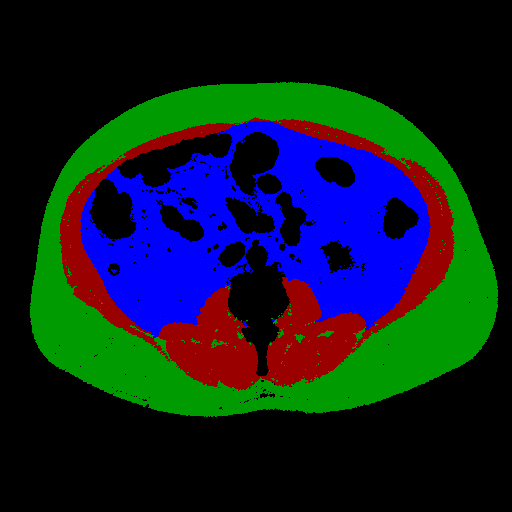

The full validation was then performed on Dataset B treating the two models as a single process that takes in a full abdominal CT series and produces estimates of body composition in terms of square cross-sectional area of muscle, subcutaneous fat, and visceral fat. In this case, the DSC is not an appropriate measure because the segmentation may be performed on a different slice from the ground truth mask. Table 2 compares the accuracy of the different tissue types and Figure 3 shows some example outputs.